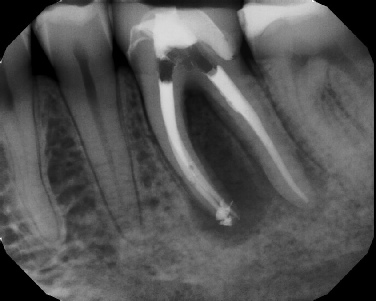

COMPLICATED ANATOMY LARGE LESIONS CALCIFIED CANALS PERFORATION / RESORPTION SEPARATED INSTRUMENTS SURGICAL CASES RETREATMENT / pOST REMOVAL OPEN APICES ACCESS THRU CROWNS Root Canal Case Portfolio

Pre-op Post-op 6 mos.